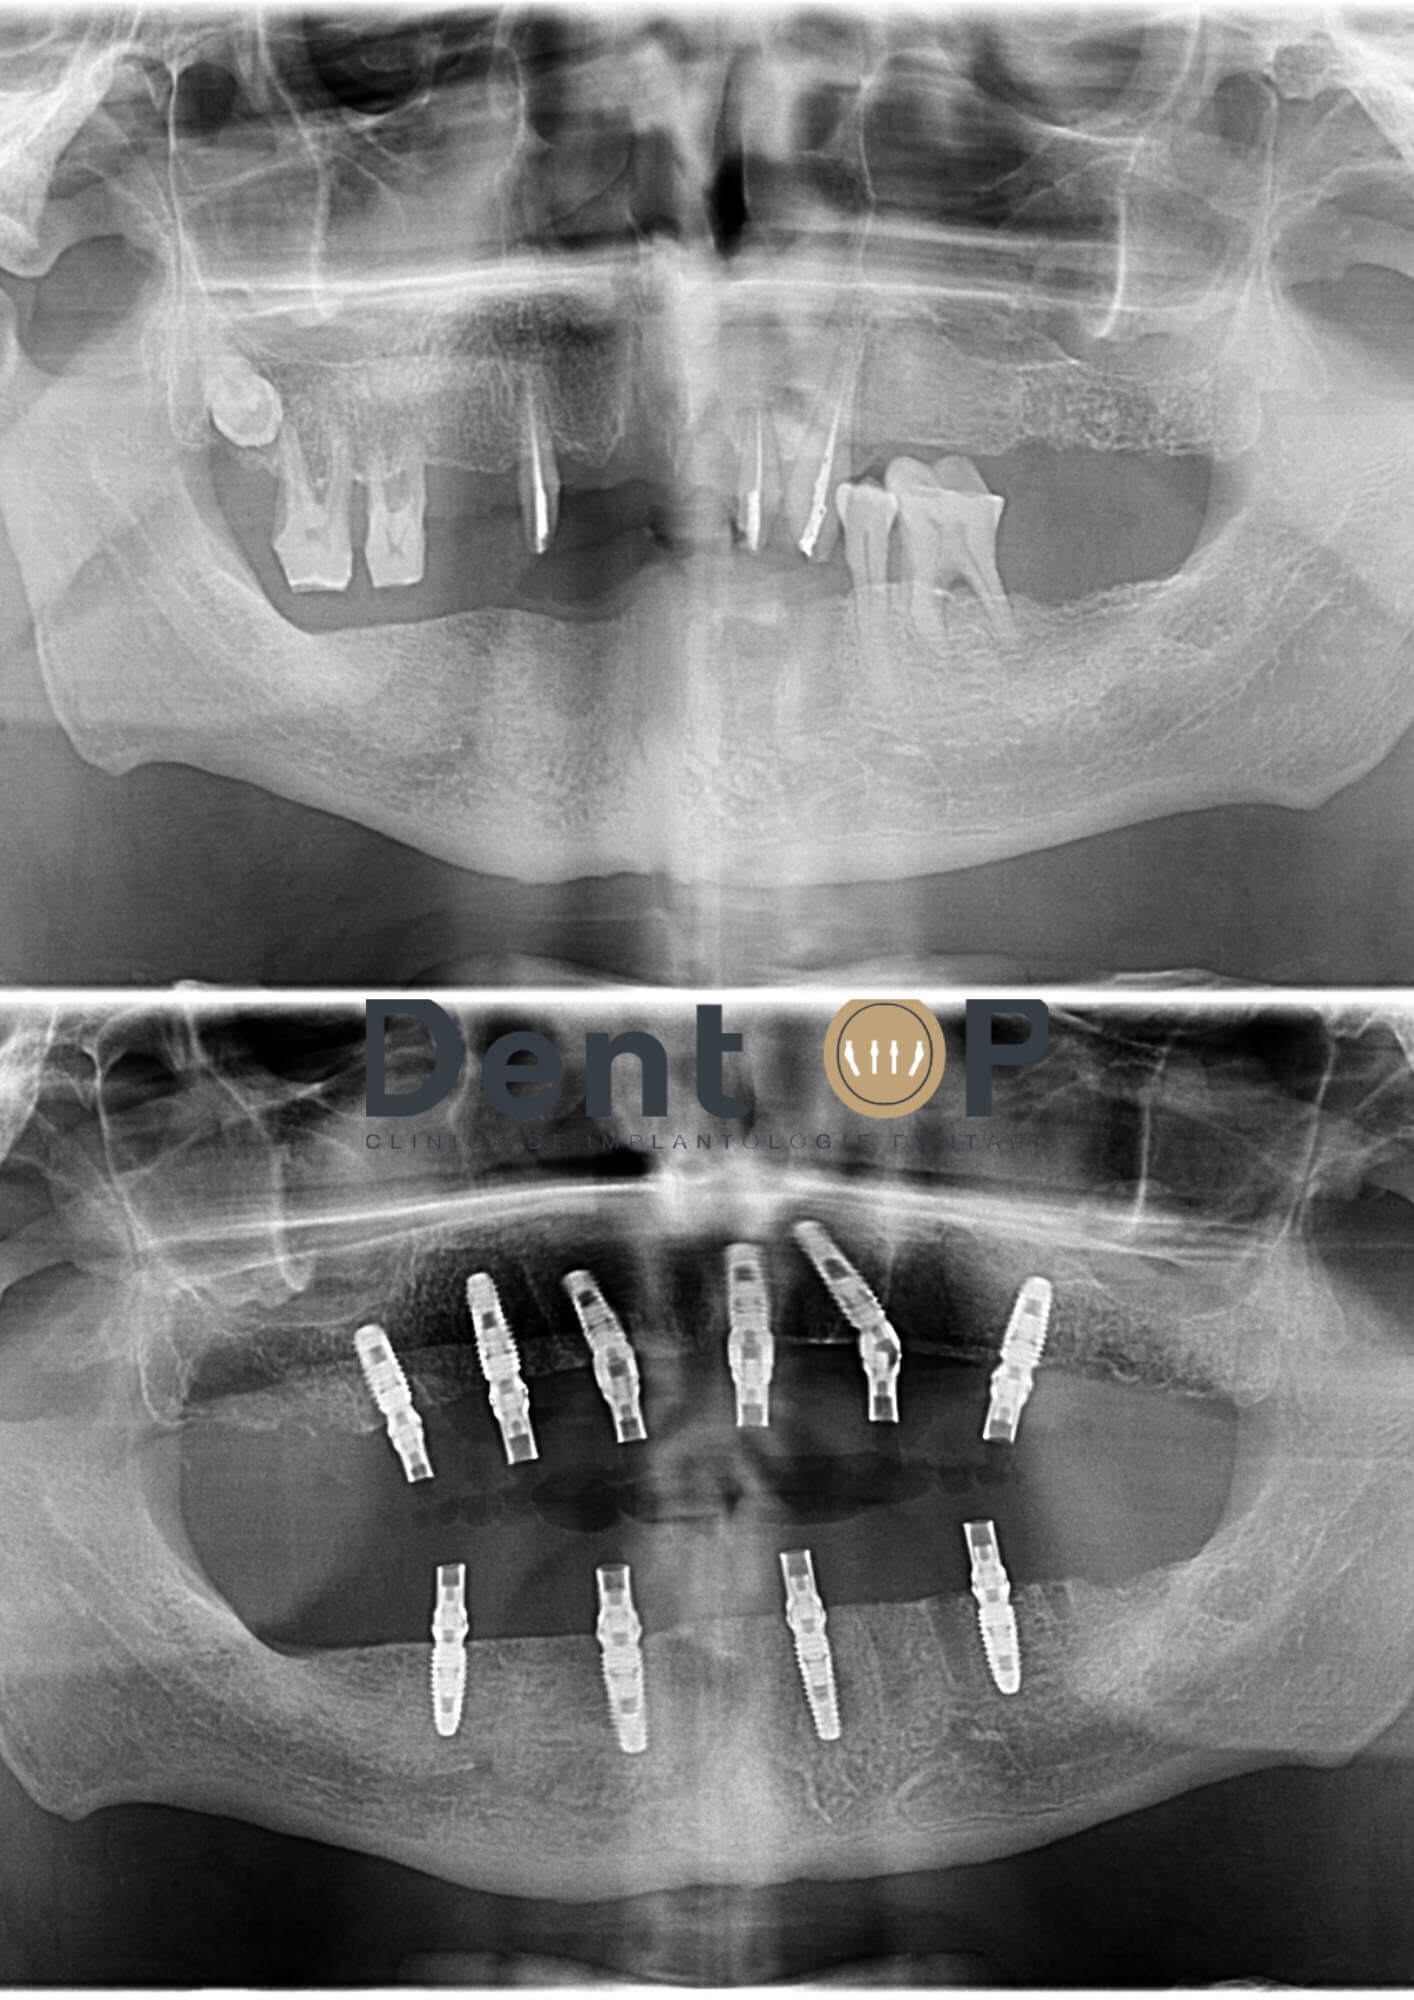

Încă de la prima consultație, Dr Cazacu Corrado a decis extragerea tuturor dinților rămași care erau afectați și inserarea de implanturi dentare pe care să stea apoi o lucrare fixă.În radiografia de mai jos vom observa dantura pacientului înainte și după ce au fost inserate cele 10 implanturi dentare atât la maxilar cât și la mandibulă.